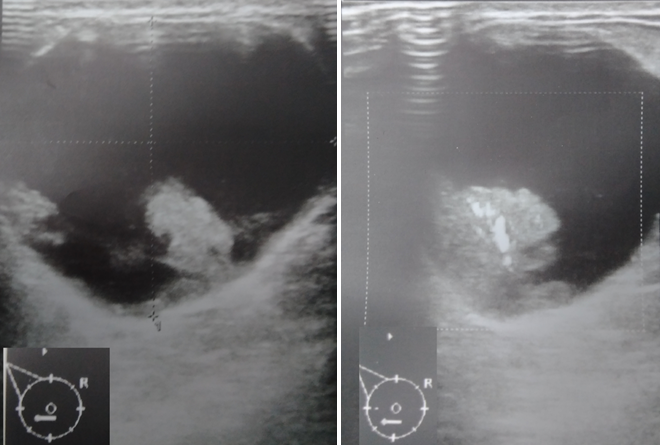

Afectan a un amplio rango de edades, aunque los carcinomas papilares son infrecuentes en menores de 30 años2. Su presentación clínica habitual es en forma de secreción serosanguinolenta unilateral por pezón, usualmente sin masa palpable. Los estudios imagenológicos muestran una lesión retroareolar, bien delimitada, aunque en ocasiones pueden ser múltiples (Figura 1)3.

Figura 1. Ecografía de mama modo B y doppler a color de lesión papilar intraquística